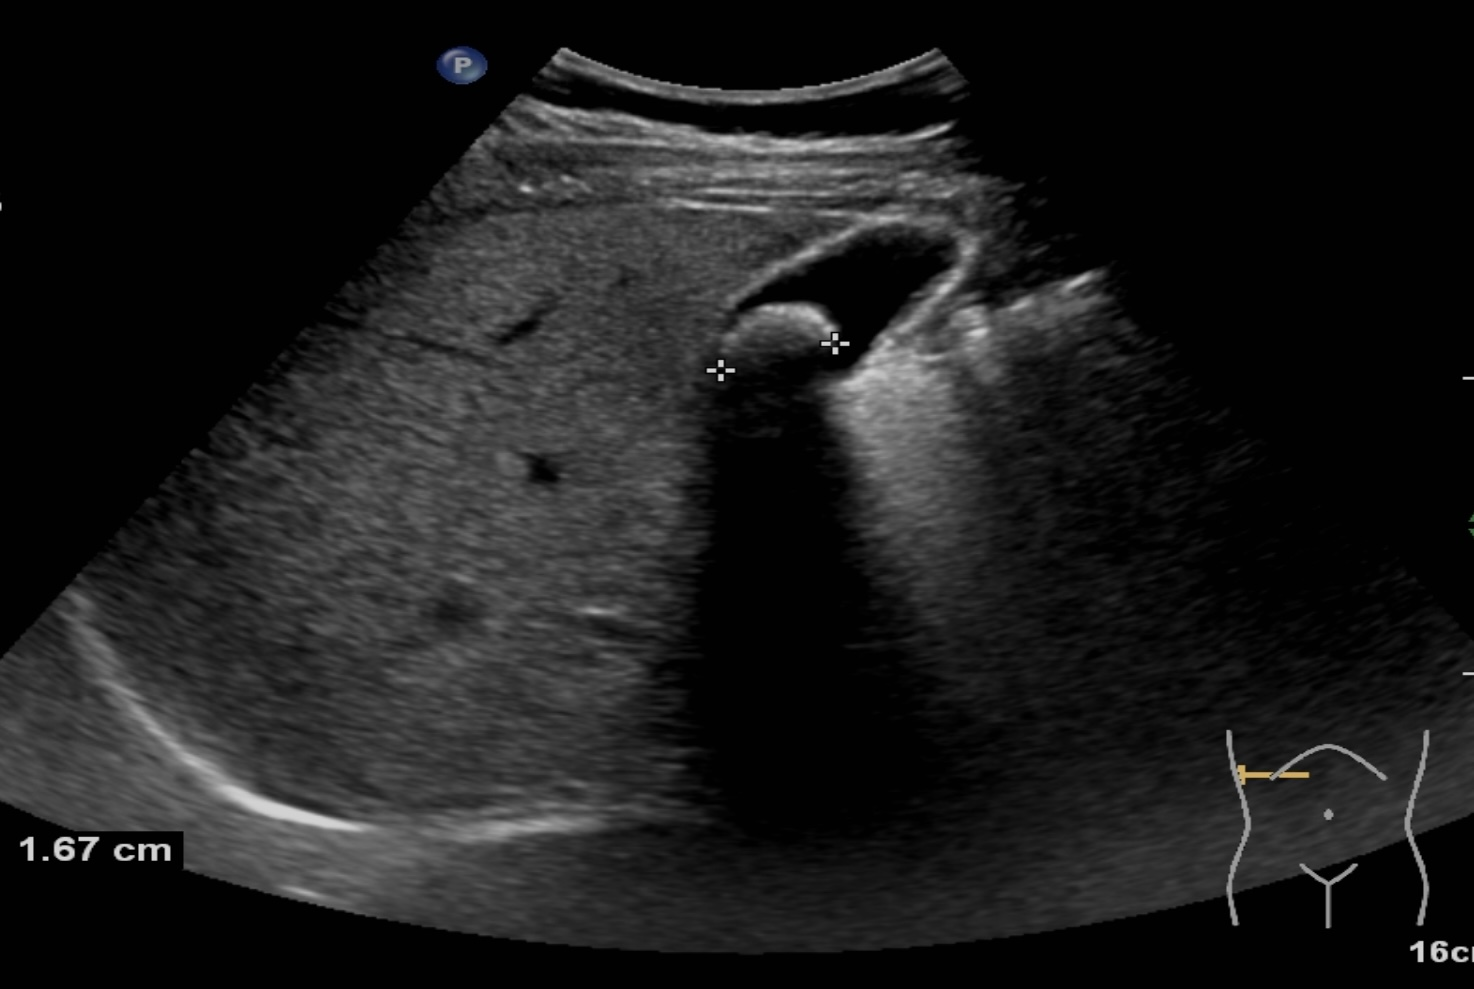

胆结石诊断方式很多,包括彩超、CT、核磁共振、胆管造影等方式都可以对胆道结石进行诊断,但是彩超具有无创、无痛、无辐射、廉价、快速、可重复性强等优点,在临床上被广泛应用作为胆结石的首选诊断方式。注意做肝胆彩超检查必须要空腹,才能准确检查出胆道结石哦!

胆囊结石超声图像 | |